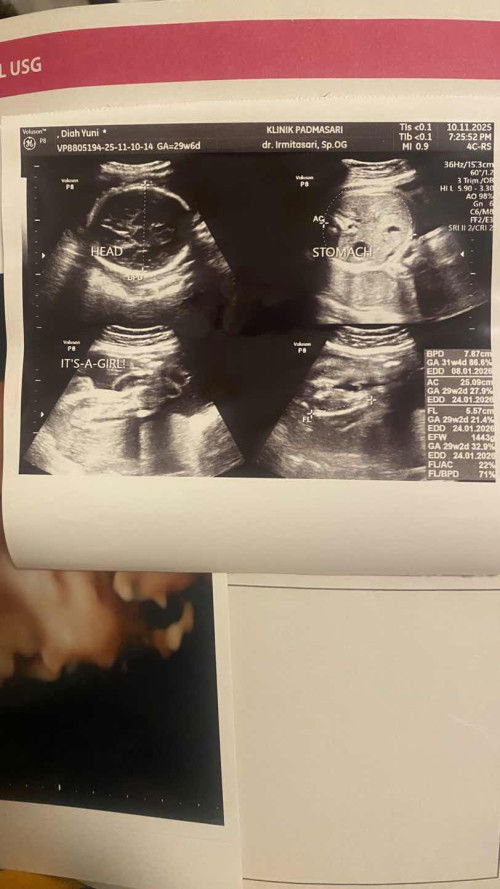

Hai bunda2, aku mau sharing persoalan perut kecil saat hamil. Selama beberapa bulan aku sempet khawatir karena teman2 ku hamil pada besar2 perutnya, alhamdulillah kekhawatiran ku terbuang saat ter usg semalam dan konsultasi sama dokter. Jadi aku TB 163cm, BB 59,8 kg sebelum hamil BB 48,6 kg. Di bulan ini aku masuk TM 3 dan perutku belum sebesar orang2 lain, hasil konsultasi ku debayku sehat bbj nya bagus 1,443gr di usia 29w6d. Dan mau lanjutin konsumsi protein hewani tiap hari untuk stabilitas kesehatan janin serta jaga HB supaya normal semuanya.🤗 Dokter menjelaskan orang yang hamil besar itu karena faktor ibunya yang BB ny lebih dari 65kg bakalan keliatan gede juga perutnya karena lemakny tebal. Sedangkan di aku lemakku tipis dan BB ku under 60 tapi normal semua alhamdulillah posisi janin juga sudah dibawah kepalanya, letak plasenta dan air ketuban bagus. Untuk bunda2 yang dikatain orang2 hamil kok perutnya kecil jangan overthinking ya bunda, kalau kita makan makanan sehat dan bergizi dan minum multivitamin, banyak minum air putih serta istirahat cukup pasti debay nya sehat dan normal. Karena saya dari awal hamil sering dikatain nggak kaya hamil karena perutnya nggak gede2. Semoga pengalamanku ini membantu ya bunda2. ❤️❤️ #sharing #jomkongsidengansayapengalamanibu2semua